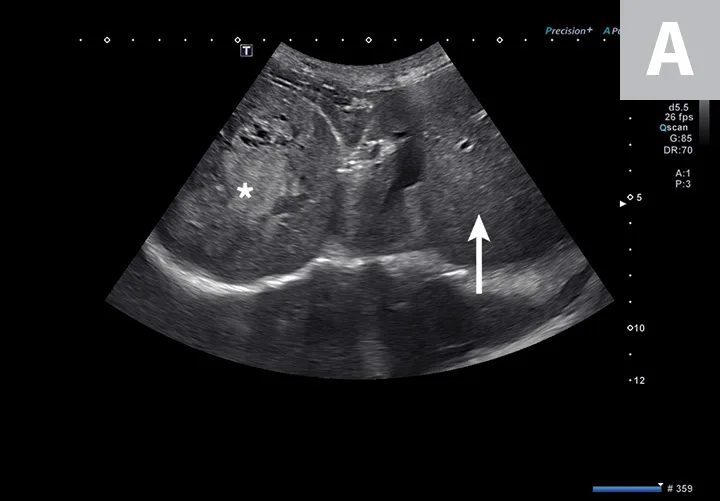

FIGURE 3

Transverse image of the right liver in a dog with a hyperechoic and multicavitary liver mass (A; asterisk) adjacent to a normal portion of liver (arrow). Deep (ie, bottom of the image) to the liver and the mass, the diaphragm appears as a hyperechoic line. Hypoechoic mass (B; asterisk) protruding from the splenic capsule.